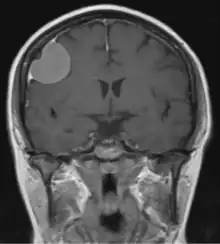

The dural tail sign (also known as "dural thickening", "flare sign", or "meningeal sign") is a radiological finding observed in magnetic resonance imaging (MRI) studies of the brain that refers to a thickening of the dura mater immediately adjacent to a mass lesion, such as a brain tumor.[1] Initially, the dural tail sign was thought to be pathognomonic of meningioma, a slow-growing tumor that arises from the meninges.[1] However, subsequent studies have shown that it can also be observed in various intra- and extra-cranial pathologies and in spinal lesions.[1] It is not a completely sensitive finding, as it is seen in only 60-72% of cases.[2] It is not completely specific either, as it has been described associated with lesions like neuromas, chloromas, pituitary diseases, granulomatous disorders, cerebral Erdheim-Chester disease, lymphomas, metastasis, hemangiopericytomas, schwannomas, and gliomas such as glioblastoma multiforme (GBM).[2][3] The final diagnosis should be further established through cerebrospinal fluid analysis or histopathological examination following a biopsy.[3]

The dural tail sign was first described in 1989 by Wilms et al..[1][4] Histopathological correlation from different studies has at times revealed tumor infiltration into the dura mater, however, in most instances, it signifies a hypervascular, non-neoplastic response.[3]